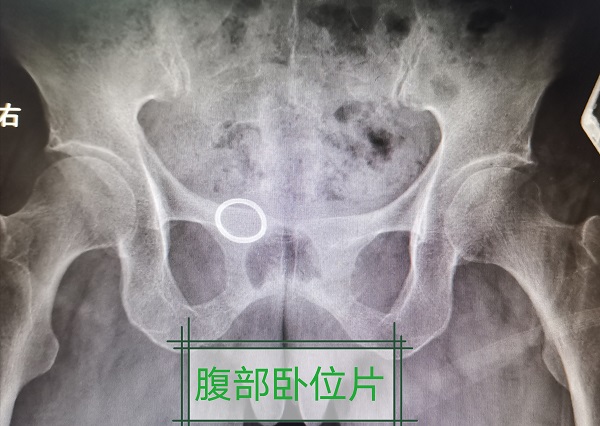

2020年06月09日,一位73岁绝经后老年女性因“反复下腹胀”于我科就诊。妇科超声检查发现宫底下方环状金属强回声。腹部立位片示宫内节育器位于盆腔中线右侧,卧位片示子宫节育器。

中心距正中线约20mm,距耻骨联合上缘约15mm。于2020年06月11日在全身麻醉下行腹腔镜下取环术。术中见右后侧盆壁近右侧骶韧带处见一金属圆环影,一半露于浆膜下。